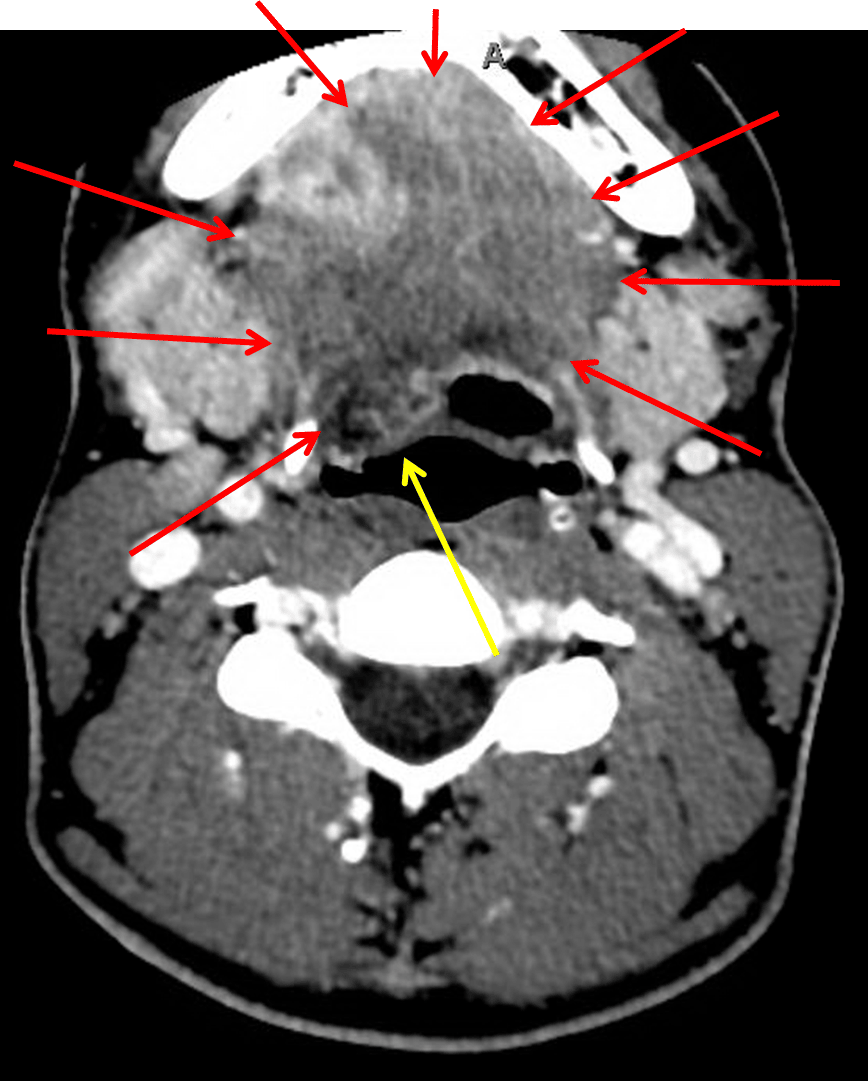

Findings

- Periapical lucency involving the right second mandibular molar with lingual surface cortical breakthrough

- Complex, peripherally enhancing collection extends from this area of cortical breakthrough inferomedial into the floor of mouth with extensive surrounding edema

- Edematous tissue bulges into the right eccentric vallecula without substantial airway narrowing

- Reactive enlargement of right greater than left cervical lymph nodes

Diagnosis

Ludwig angina

Periapical lucency associated with the right second mandibular molar complicated by lingual cortex breakthrough and an associated abscess extending into the floor of the mouth, concerning for Ludwig angina. Surrounding edematous tissue bulges into the right eccentric vallecula without substantial airway narrowing. Recommend urgent ENT consultation.

Fluid extending along the right floor of the mouth (red arrows). Mass effect on the pharynx (yellow arrow).